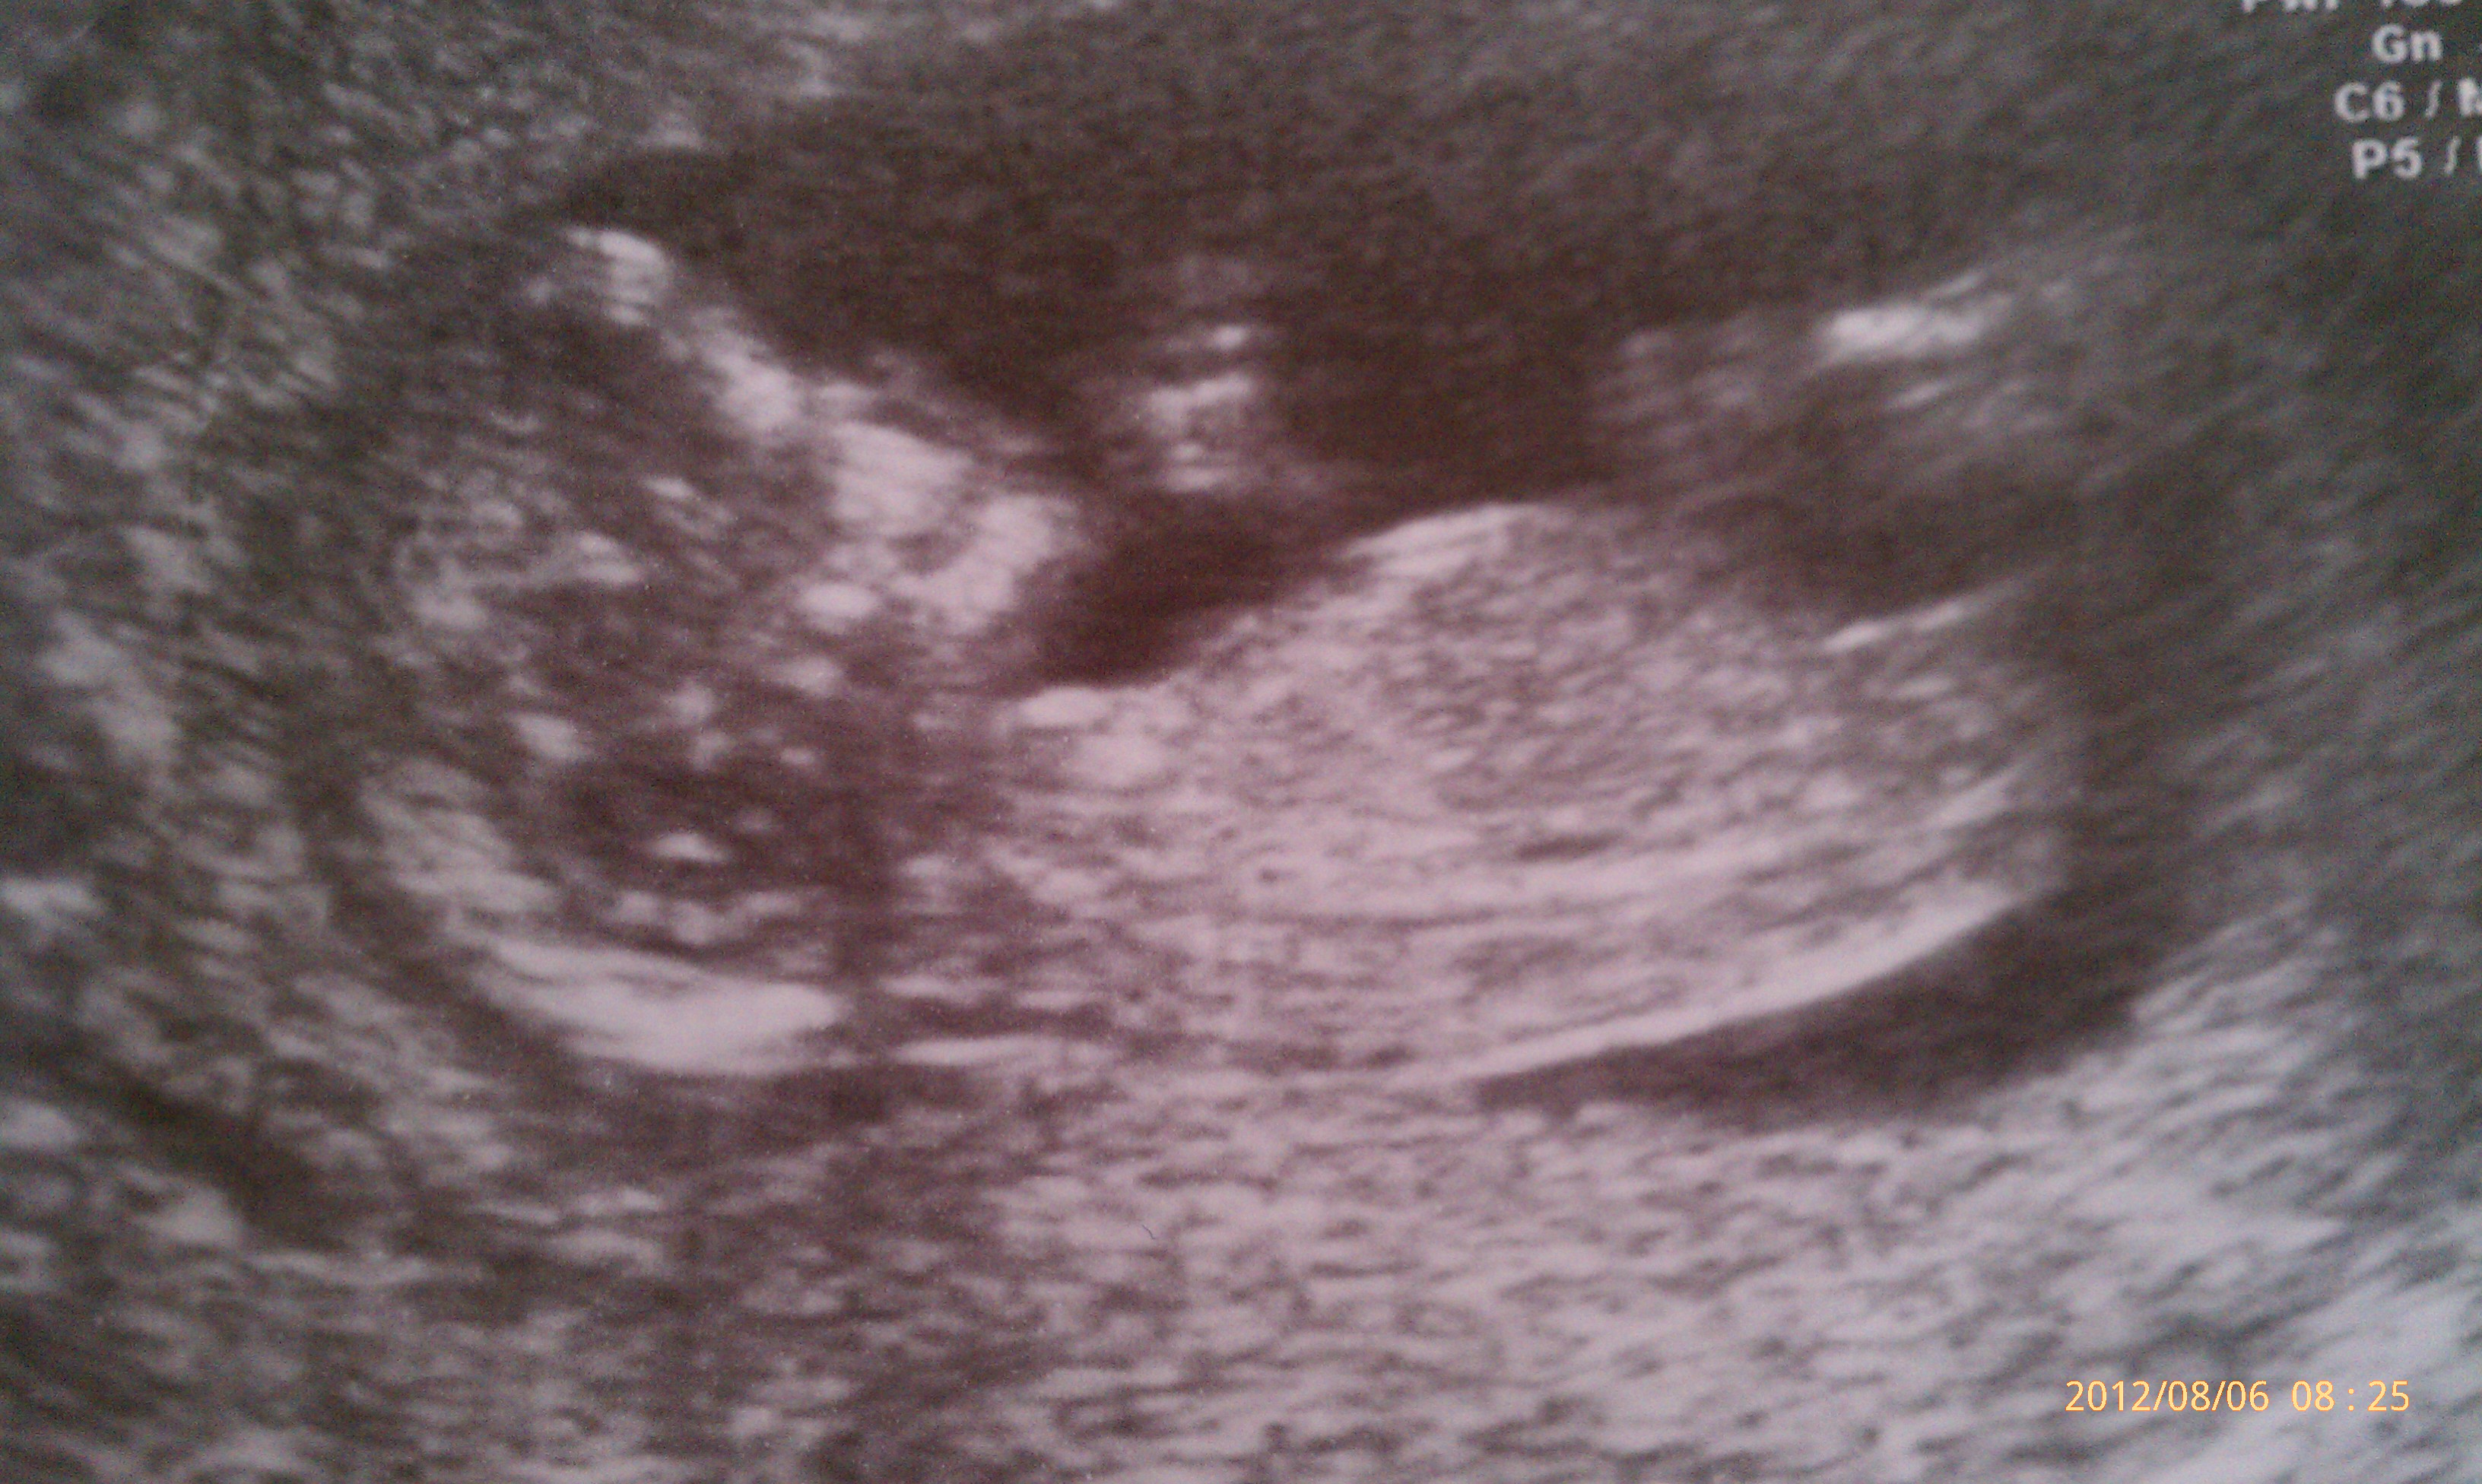

Just had my first trimester scan. Wondering if someone can help determine the baby's sex?

Going to say boy.

I guess girl

Thank for your response! I hope it is a boy I already have a girl but I'll be satisfied with anything <3 2 is enough for me :) Do you think it's a good pic or should I post another one?

Girl by skull and nub :DD:

lean girl

GIRL

I'd say girl xxx

I'd guess girl.